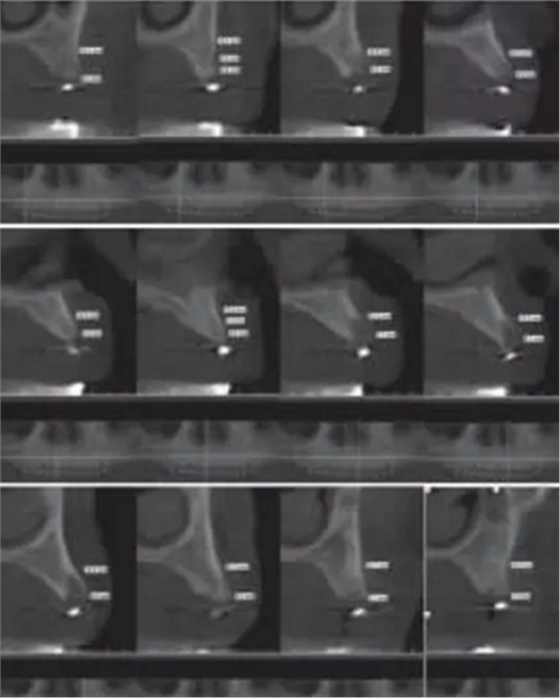

1.2.3治療過程:先行微創(chuàng)拔除14、13、21、22、23、24及25,搔刮拔牙窩去除炎癥組織,常規(guī)制作一副上頜過渡義齒(圖4,5)。2個(gè)月拔牙術(shù)后復(fù)診,利用上頜過渡義齒作為個(gè)性化托盤取上頜模型并翻制石膏模型,在石膏模型上根據(jù)過渡義齒標(biāo)出各個(gè)牙位,同時(shí)利用壓膜機(jī)制作放射性模板(如圖6)?;颊吲宕鞣派湫阅0迮臄z全景片及CBCT(如圖7、8)。

圖8 佩戴放射性模板CBCT

根據(jù)所得信息將制定16、13、23及26為種植體位置行all-on-4種植手術(shù)。種植手術(shù):常規(guī)消毒、鋪巾,甲哌鹽酸阿替卡因局部浸潤局麻下,患者戴上去除牙膠并已消毒后的放射模板,在16、13、23及26位置用球鉆定位(圖9、10、11、12),行微創(chuàng)切口(圖13),從17至12和從27至22的切口,并在所定位置逐級(jí)備洞,分別在13、16、23及26各植入一枚Nobel Replace Conical Connection 4.3mm*13mm種植體,同時(shí)在13、23接30°復(fù)合基臺(tái),在16、26接復(fù)合直基臺(tái)(圖14)。嚴(yán)密縫合后行即刻修復(fù)(圖15、16、17、18)。

放射性模板是指帶有放射性阻射標(biāo)記物的模板,在患者種植手術(shù)前戴入口內(nèi)并進(jìn)行放射性拍攝,可評(píng)估種植位點(diǎn)骨質(zhì)及可用骨量,從而設(shè)計(jì)種植體的數(shù)目、位點(diǎn)及方向,指導(dǎo)最終手術(shù)方案。放射性模板能顯示種植位點(diǎn)或未來修復(fù)體的信息,它的組織面需與其下方的粘膜緊密貼合且在放射性拍攝過程中保持穩(wěn)定位置。本病例首先按照全口修復(fù)計(jì)劃,給患者制作上頜過渡義齒。利用過渡義齒作為個(gè)性化托盤取模翻制石膏模型,并在石膏模型上按照過渡義齒標(biāo)記牙位,繼而使用真空壓膜機(jī)制作樹脂薄膜導(dǎo)板,然后在樹脂導(dǎo)板相應(yīng)牙位打孔并填塞放射性顯影的材料如牙膠?;颊吲鍘Х派湫阅0暹M(jìn)行錐形束CT(CBCT)的掃描,從而得到種植位點(diǎn)骨組織的情況。牙列缺失的患者其放射性模板由粘膜支持,有可能在放射性掃描的過程中移位,可使用咬合記錄進(jìn)行固定。本病例所制作的放射性模板與患者的粘膜較為貼合,有較強(qiáng)的固位力。

傳統(tǒng)導(dǎo)板一般是用熱壓膜技術(shù)制作的。首先應(yīng)該給患者常規(guī)取模并灌注石膏模型,在石膏模型上根據(jù)患者咬合關(guān)系以及牙槽嵴的情況制作蠟型,然后再翻制石膏模型,繼而利用真空壓膜機(jī)制作樹脂薄膜導(dǎo)板,將導(dǎo)管放置種植體植入的理想位置并與導(dǎo)板結(jié)合一起。傳統(tǒng)導(dǎo)板制作方法簡單,價(jià)格便宜,在一定程度上考慮了種植修復(fù)后的效果和頜骨的解剖結(jié)構(gòu),但對(duì)于牙列缺失或骨量不足的情況下所提供的信息較為局限。本病例利用放射性模板獲得種植位點(diǎn)骨密度、可用骨的高度寬度以及種植體位置與重要解剖結(jié)構(gòu)的位置關(guān)系等信息后將放射性模板的牙膠去除并進(jìn)行消毒,戴入患者口內(nèi)作為外科導(dǎo)板按照術(shù)前設(shè)計(jì)的種植位點(diǎn)用球鉆定位并在最佳骨質(zhì)及骨量位置行種植手術(shù),種植體都獲得較好的初期穩(wěn)定性,并行即刻修復(fù)。放射性模板在術(shù)中不能準(zhǔn)確定向,本病例患者在制作即刻修復(fù)后可見臨時(shí)義齒種植體穿孔位置在近遠(yuǎn)中方向跟術(shù)前設(shè)計(jì)幾乎一致。同時(shí)本病例在種植位置定位后采用微創(chuàng)切口,使患者術(shù)后腫脹及疼痛減少。將放射性模板作為種植簡易導(dǎo)板應(yīng)用于上頜無牙頜種植修復(fù),其效果好,價(jià)格便宜,術(shù)后并發(fā)癥小,是值得推薦的一種上頜無牙頜種植手術(shù)方案。